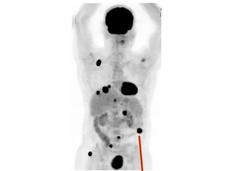

Changes in Metabolism Help Melanomas Spread

Melanoma cells that metastasize to other parts of the body produce high levels of a protein called MCT1, a new study in mice has found. Blocking MCT1 with an investigational drug, AZD3965, led to fewer and smaller metastatic tumors.